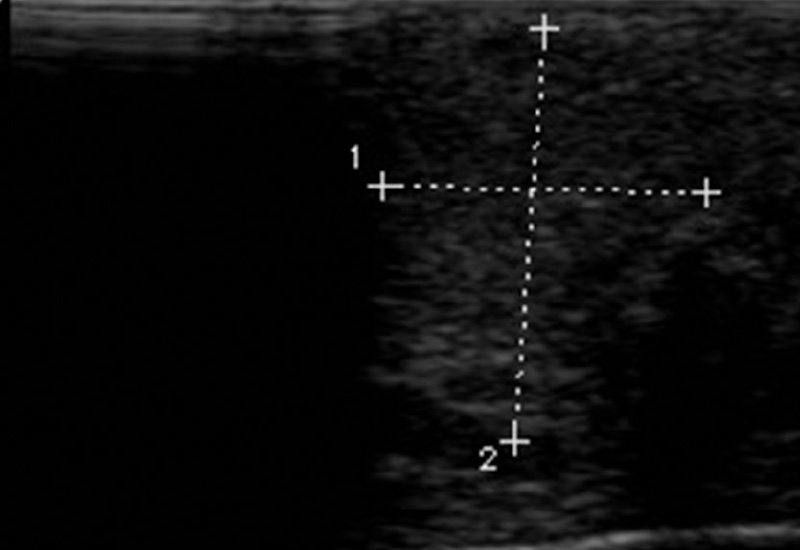

SONOGRAFIE: Die Sonografie ist ein besonders wertvolles, nicht-invasives Verfahren zur frühen Diagnose der tophösen Gicht. Sie ermöglicht die direkte Visualisierung von Harnsäurekristallen in Gelenken und Weichteilen. Ein charakteristisches Merkmal in der Sonografie ist das Doppelkonturzeichen, bei dem Harnsäurekristalle an den Gelenkoberflächen sichtbar werden. Dieses Zeichen ist hochspezifisch für Gicht und hilft, sie von anderen entzündlichen Erkrankungen zu unterscheiden. Die Sonografie eignet sich besonders gut für die frühzeitige Erkennung von Harnsäureablagerungen, was bei Frauen, die oft später im Leben an Gicht erkranken, von großer Bedeutung ist. Im Einzelfall können kortikale stanzförmige Defekte sonografisch dargestellt werden.